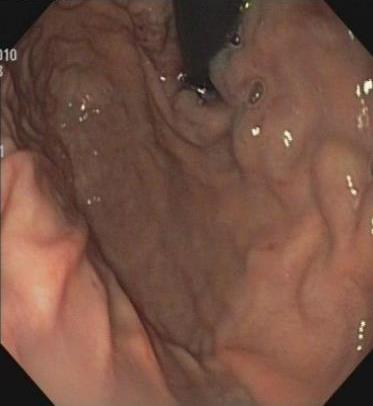

摘要:目的 探讨获得性免疫缺陷综合征(AIDS)合并马尔尼菲篮状菌(TM)感染导致肠道感染的内镜下特征。方法 回顾性分析2022年11月-2024年10月于该院确诊为AIDS合并TM感染导致肠道感染的6例患者的临床资料。包括:临床症状、实验室检查、影像学检查、内镜检查和病理检查等。结果 6例患者中,男5例,女1例;发病年龄26~67岁;AIDS合并TM感染导致肠道感染患者的临床表现为:腹泻、腹痛、腹胀和恶心呕吐。其中,2例有消化道出血表现。实验室检查:6例患者外周血白细胞计数为(1.37~4.49)×109/L,血红蛋白计数为(67~99)g/L;CD4+T淋巴细胞为(1~52)个/μL,CD8+ T淋巴细胞为(61~321)个/μL,CD4+T淋巴细胞/CD8+T淋巴细胞比值为(0.01~0.18)。6例患者均行HIV RNA检测。其中,5例HIV RNA阳性。血培养:可见丝状真菌,报告显示为TM。影像学检查:6例患者CT结果可见肠系膜及腹膜后多发淋巴结肿大。内镜检查:6例患者内镜下均可见肠道病变。其中,十二指肠糜烂溃疡2例,结肠多发糜烂溃疡4例。病理检查:6例患者幽门螺杆菌(Hp)结果均为阴性,黏膜下可见成簇的小球形真菌孢子,符合TM感染;特殊染色:PAS(+),六胺银染色(+)。结论 当AIDS晚期患者出现消化道症状时,应警惕TM感染,病变部位常见于全结肠和直肠,亦可累及十二指肠,内镜下表现多为溃疡、糜烂和隆起性病变,形态表现无特异性;及时行胃肠镜检查、病理活检、特殊染色和免疫组化是确诊的关键。